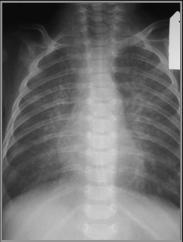

Hypoplastic Left Heart Syndrome